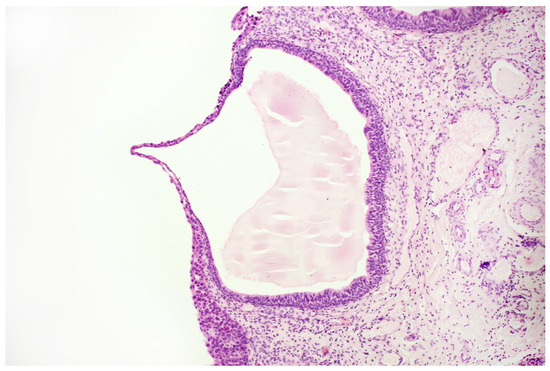

Bladder cancer is one of the most common cancers in global statistics. One of the issues associated with this disease is the high incidence of cases with delayed diagnosis and what factors correlate with worse treatment outcomes. A possible reason for this may be the rather limited availability of non-invasive diagnostic tools. This short communication presents a case of a 68 year old male patient after an ineffective therapy, carried on for several years with symptoms commonly associated with prostate overgrowth that masked a carcinoma in situ of the urinary bladder. Implementation of several diagnostic techniques, including urine sediment cytology, immunocytochemistry, the fluorescence in situ hybridisation technique, the Bladder EpiCheck test and whole-genome sequencing, enabled the establishment of a correct diagnosis, implementation of appropriate treatment and provision of patient-friendly monitoring. The described case emphasises the usefulness of cell-based and liquid-based urine tests in bladder cancer diagnostic procedures. Full article

The Bladder EpiCheck Test as a Non-Invasive Tool Based on the Identification of DNA Methylation in Bladder Cancer Cells in the Urine: A Review of Published Evidence

Recently, there has been a great effort to develop tests based on non-invasive urinary biomarkers (NMIBCs). These tests are based on the fact that NMIBCs are heterogeneous at the molecular level and can be divided into different molecular groups useful to predict prognosis and response to treatment. The assessment of epigenetic alterations, such as DNA methylation, represents a promising cancer biomarker. DNA methylation is an epigenetic modification that affects gene expression without modifying the DNA sequence. Several studies have highlighted the presence of methylated loci in the context of bladder cancer, indicating its potential application as a diagnostic and prognostic biomarker. One of the novel assays based on a DNA methylation profile, the Bladder EpiCheck, analyzes DNA from spontaneous urine, detecting disease-specific DNA methylation patterns in bladder cancer patients. This test, due to its non-invasive nature and highly promising performance could, in future, become an invaluable tool in the follow-up of bladder cancer patients. Potential new applications could include diagnosis and surveillance of upper-tract disease, for the replacement of invasive testing and ureteroscopy. Full article